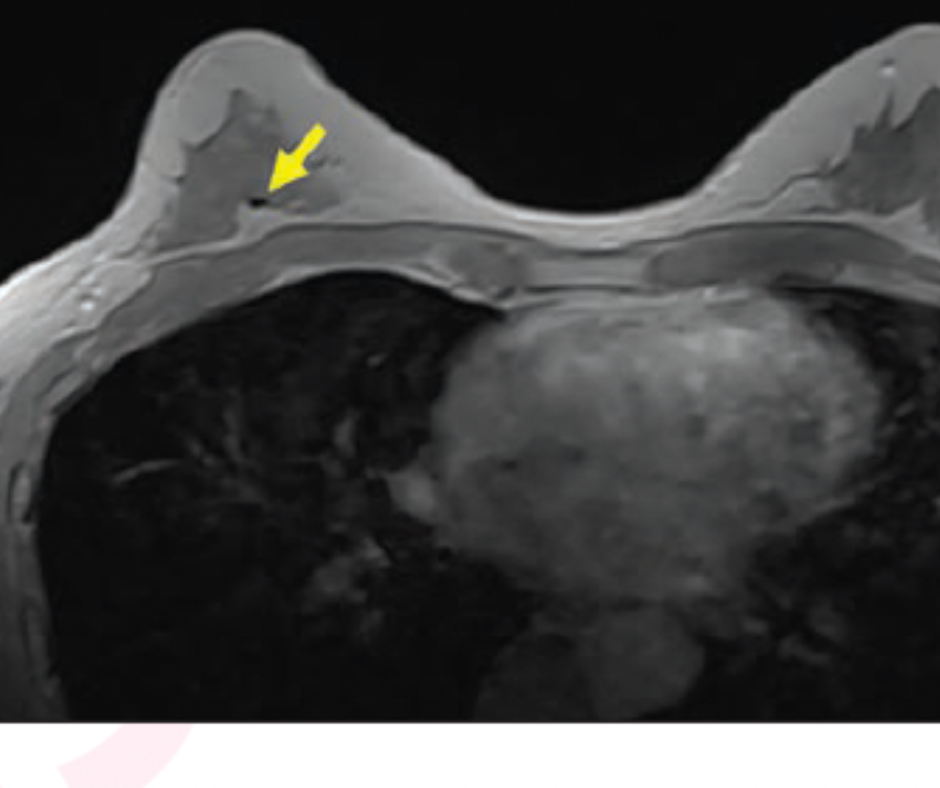

For some patients, identifying biopsy clips on breast magnetic resonance imaging (MRI) may be challenging due to variabilities in the size and shape of the biopsy clips, associated susceptibility artifacts and the types of sequences and acquisition parameters.

“Fat suppression … is undesirable when identifying biopsy clips because it causes the fat in the breast to become hypointense and therefore closer in signal intensity to the biopsy marker clip,” pointed out Baker and colleagues. “In addition, the administered contrast media reduces anatomic noise by increasing the signal intensity of fibroglandular tissue to approach that of relatively hyperintense fat, thereby reducing the variability of signal intensities present in the underlying breast tissue.”